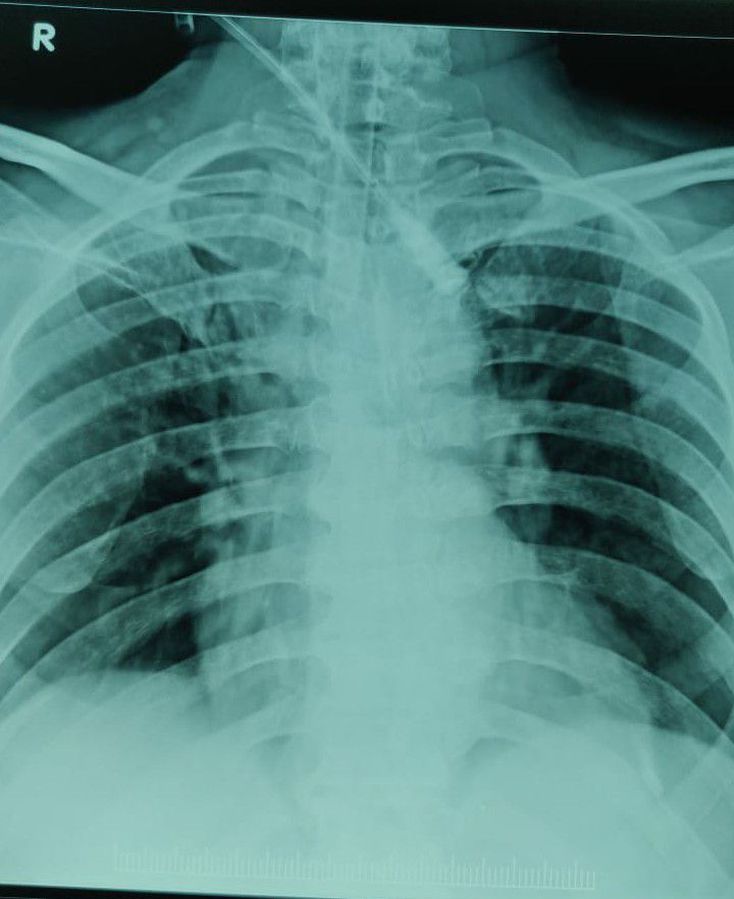

Interpretation 58 yr old male poioson consumption phenthoate along with alprax 0.5mg 10 tablets and metformin 10 tablets,pt treated and stabilised for 24hrs and then saturation falls E.M doctor advised for ventilatory support,but he explained about weekening of chest muscles

Phentolate is an insecticide used widely for agri farming 100 ml bottle consumed all of it